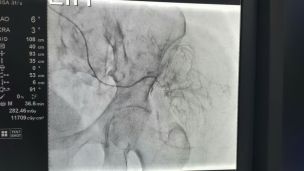

TomoClinic тепер проводить комп'ютерну томографію в режимі 4D

З радістю повідомляємо нашим пацієнтам гарну новину: томограф TOSHIBA AQUILION LB допомагає пацієнтам з новоутвореннями легенів в підготовці до променевої...